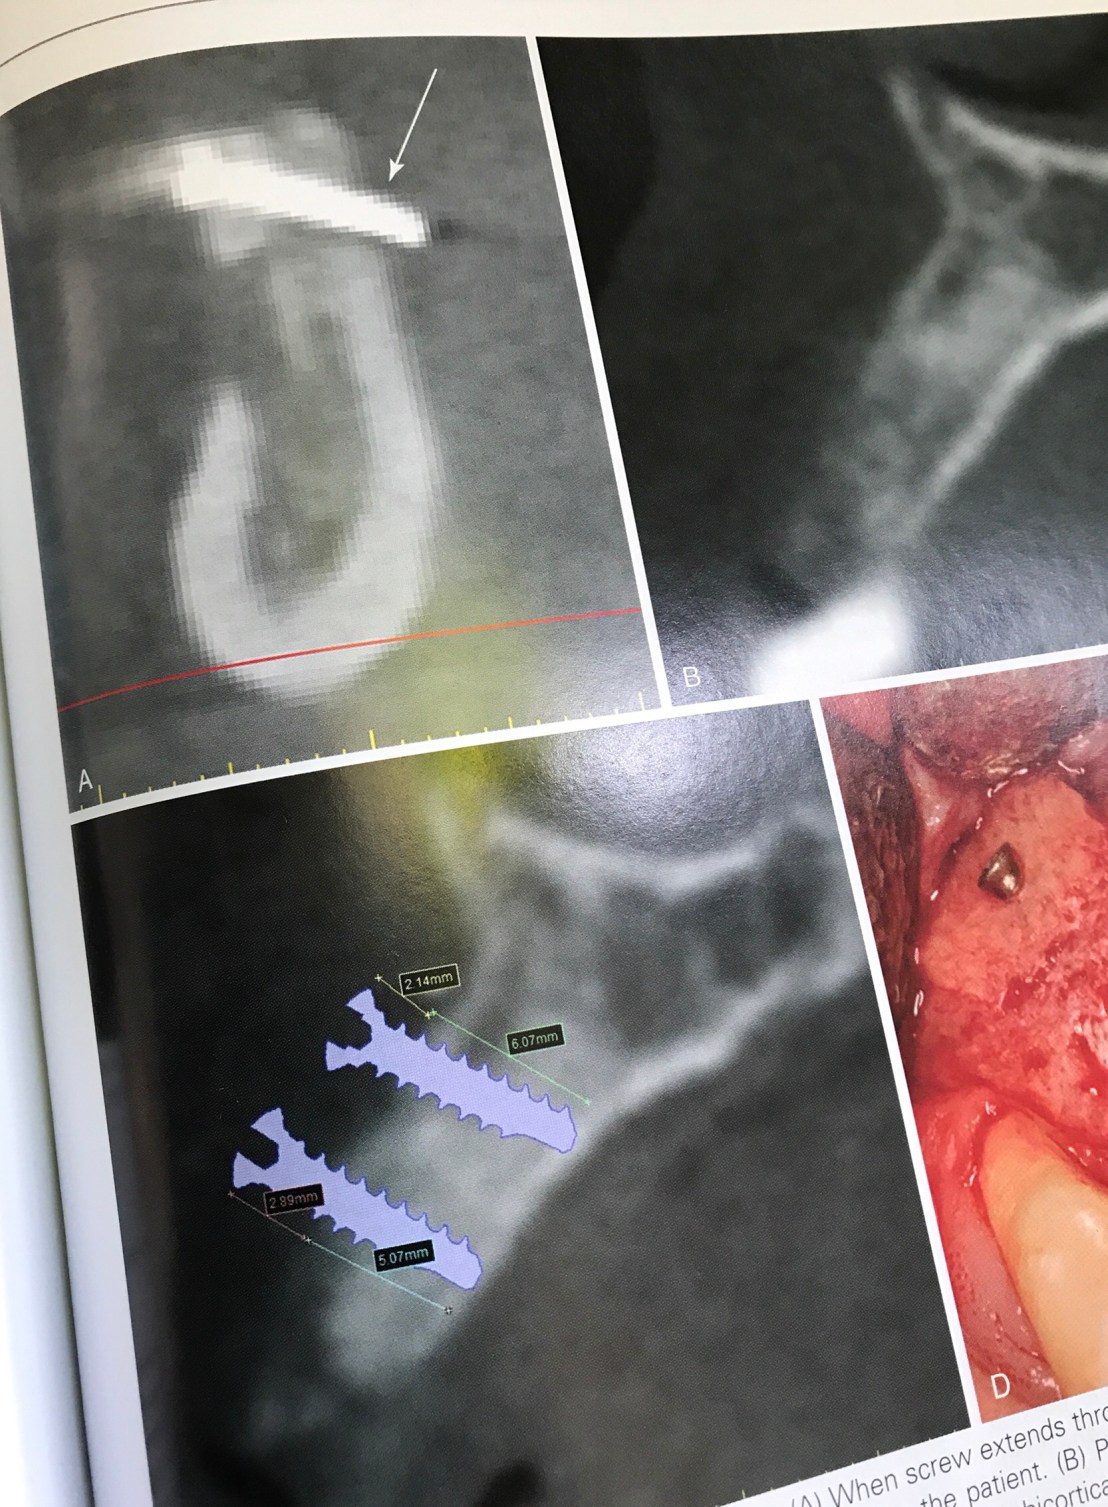

เคสนี้กลัว Graft ขยับครับ ใช้ screw ยาวจนทะลุ lingual cortical plate

ตำแหน่งที่ลูกศรชี้ในรูปแรกคือหาง screw ที่ทะลุด้าน lingual

ส่วนรูปร่าง แสดงการใช้ CBCT หาความยาว screw แบบความยาว ideal คือ ยึดจาก buccal cortical plate ถึง lingual cortical plate พอดี